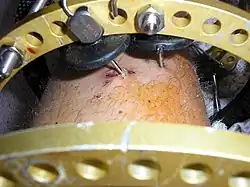

External fixation is a surgical treatment wherein Kirschner pins and wires are inserted and affixed into bone and then exit the body to be attached to an external apparatus composed of rings and threaded rods — the Ilizarov apparatus, the Taylor Spatial Frame, and the Octopod External Fixator — which immobilises the damaged limb to facilitate healing.[1] As an alternative to internal fixation, wherein bone-stabilising mechanical components are surgically emplaced in the body of the patient, external fixation is used to stabilize bone tissues and soft tissues at a distance from the site of the injury.

In the 1950s, in the USSR, Dr. Gavriil Ilizarov devised and developed and applied the Ilizarov apparatus for treating and resolving fractures, deformities, and defects of the bones of the limbs. A metal frame encircles the limb is attached to the underlying bone by crossing (X) pins inserted through the bone and limb. The external rings are linked to each other by threaded rods and hinges that allow to move the position of the bone fragments without opening the fracture site, then the fragments can be fixed in rigid position until complete healing.

In this kind of reduction, holes are drilled into uninjured areas of bones around the fracture and special bolts or wires are screwed into the holes. Outside the body, a rod or a curved piece of metal with special ball-and-socket joints joins the bolts to make a rigid support. The fracture can be set in the proper anatomical configuration by adjusting the ball-and-socket joints. Since the bolts pierce the skin, proper cleaning to prevent infection at the site of surgery must be performed.

The parts of an external fixator include:

- Schanz pin

- Connecting rods

- Clamps